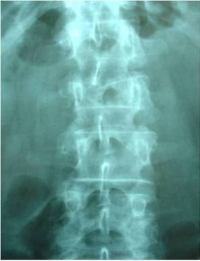

Pre- and post-operative comparison of a cemented kyphoplasty

Female, age 55, compression fracture of L2

Before 2

after 2